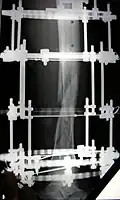

The photographs and radiographs illustrate the application and emplacement of an external fixator, an Ilizarov apparatus, to repair the open fracture of the lower left leg of a man. The photographs were taken four weeks after the patient fractured the shinbone (tibia) and the calfbone (fibula) of his left leg, and two weeks after the surgical emplacement of the Ilizarov apparatus to immobilise the leg and isolate the wound and fracture site to facilitate healing.

X-ray of the open fracture of the left leg; the external fixator was installed ca. 24 hrs. in hospital.

X-ray of the open fracture site immediately after installation of the Ilizarov apparatus.